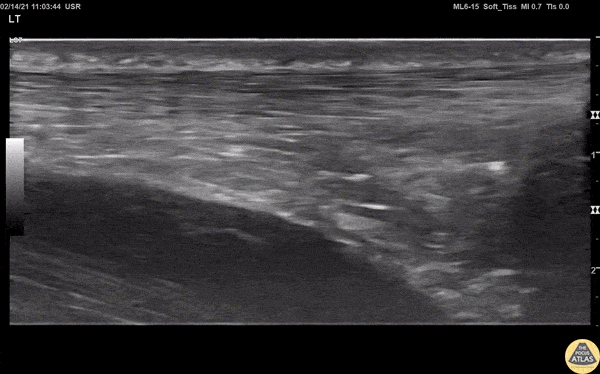

This can be visualized in both a short and long view. Pain in the tendon, good story plus ultrasound can be diagnostic. Track the tendon down using the probe. Here’s the long view with an intact and ruptured tendon.

Here’s the short view.